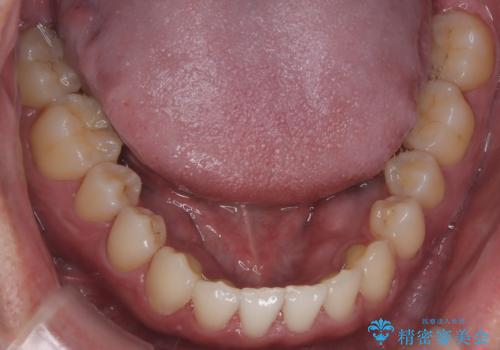

【インビザライン】前歯の隙間を治したい。

- 前歯の隙間を主訴に来院されました。

インビザラインにて治療しました。

ディープバイトも改善でき患者さんも満足されていました。

前歯の隙間だけを閉じる治療を行うだけでは、噛み合わせが悪くなるためディープバイトも改善が必要です。